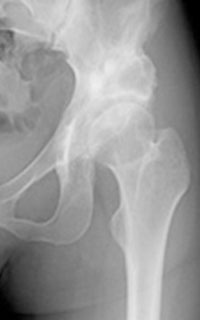

図1. 右変形性股関節症に対し, セメントレスTHAを行った症例.

大腿骨に挿入するステムにおいて、現在の日本では骨セメントを使わないセメントレス固定が主流です。ステムと骨の固着が良好であり、その結果長期成績が飛躍的に向上したためです。当科においても約80%の患者さんにはセメントレスステムを用います (図1)。また、その方の大腿骨頚部から骨頭までの長さ、捻れの角度、骨の強さなど総合的に判断し、最適と思われるステムを使い分けしています。その結果、過去23年間に行った患者さんは98%以上の確率でゆるみや感染、脱臼が発生していません。